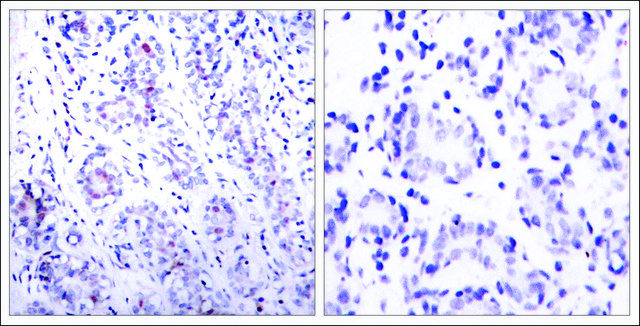

Anti-STAT3 (Ab-727) antibody produced in rabbit

IHC (p), WB

immunohistochemistry (formalin-fixed, paraffin-embedded sections): 1:50-1:100, western blot: 1:500-1:1000